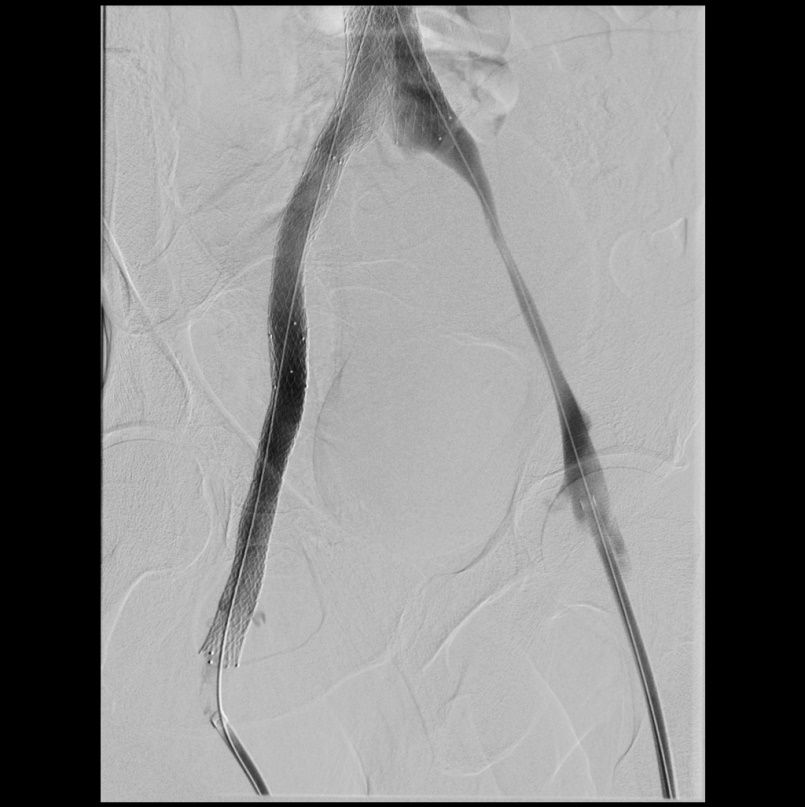

Rekanalisation mit Dilatation und Stents der rechtsseitigen Beckenvenen  (rechtes Bild). Hierdurch wieder freier Fluss in den Beckenvenen.